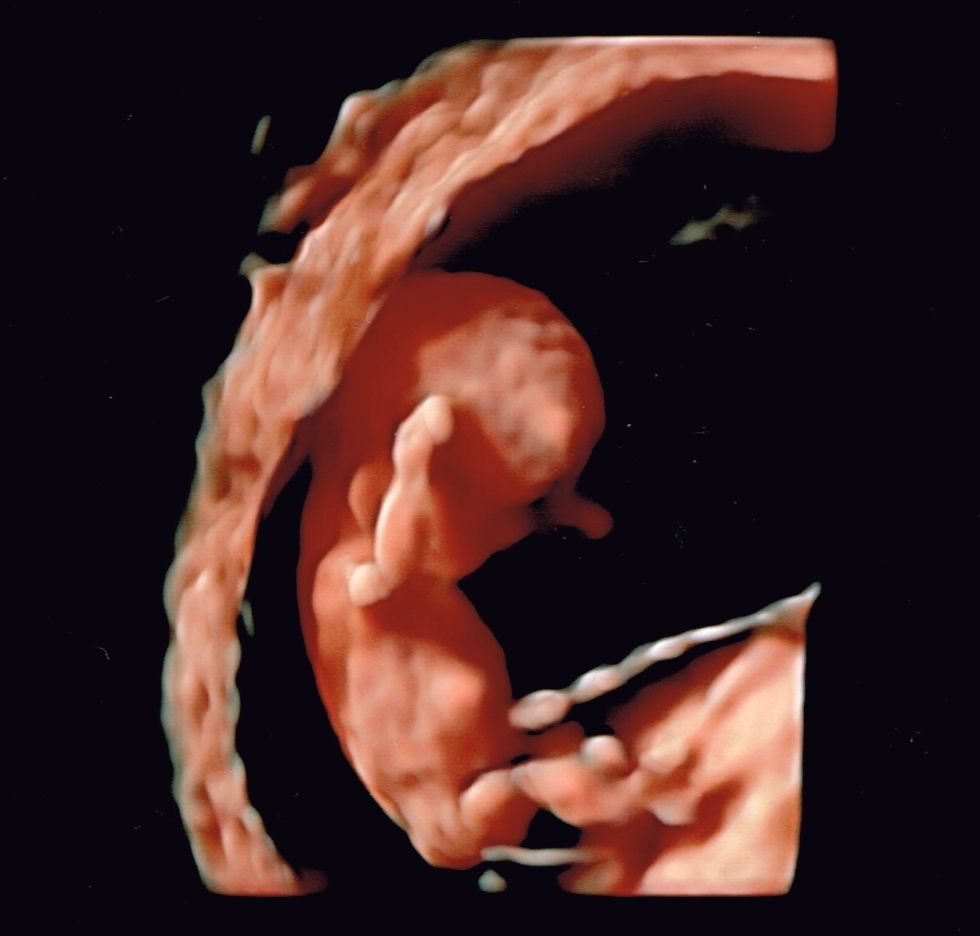

Moją pasją jest diagnostyka ultrasonograficzna w ginekologii i położnictwie, ocena anatomii płodu w badaniach prenatalnych. Nieustająco podnoszę kwalifikacje celem zapewnienia pacjentowi najlepszej opieki. Posiadam certyfikaty Polskiego Towarzystwa Ginekologów i Położników, Polskiego Towarzystwa Ultrasonografii oraz Fetal Medicine Foundation do wykonywania badań ultrasonograficznych.